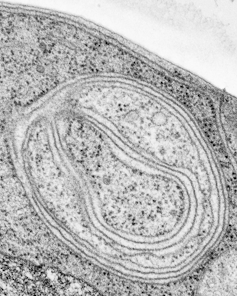

The process of autophagy starts when the cell begins to form a membrane near damaged proteins or organelles. This membrane will expand into a vesicle, or sac, known as an autophagosome, that engulfs the damaged material. It will then fuse with another internal cell structure full of acid called a lysosome that helps degrade its cargo.

Interestingly, we also observed Beclin1 at discrete points of contact between mitochondria and endoplasmic reticulum during mitophagy. This supports emerging research suggesting that physical interactions between these organelles facilitate the transfer of certain molecules needed to make autophagosomes. Our work indicates that only Beclin1 promotes engulfment of damaged mitochondria at these sites. Beclin2 may perform a different role in autophagy in other conditions.